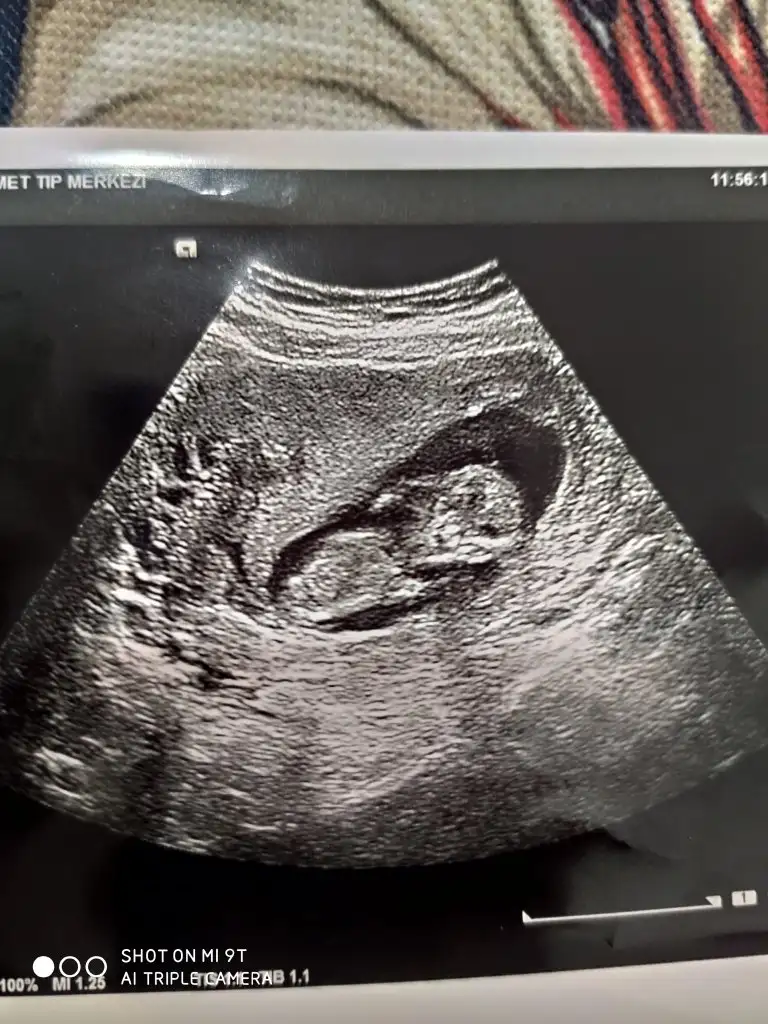

Merhaba buda 13 haftalık acaba şimdi netleşir miKarından ise erkek vajinalsa kiz tabiki en iyi 11 12 13 haftalar

Erkek görünüyorMerhaba buda 13 haftalık acaba şimdi netleşir mi

Emin olamadım başka USG varsa paylaşın sanki erkek gibi gibi ama emin değilim